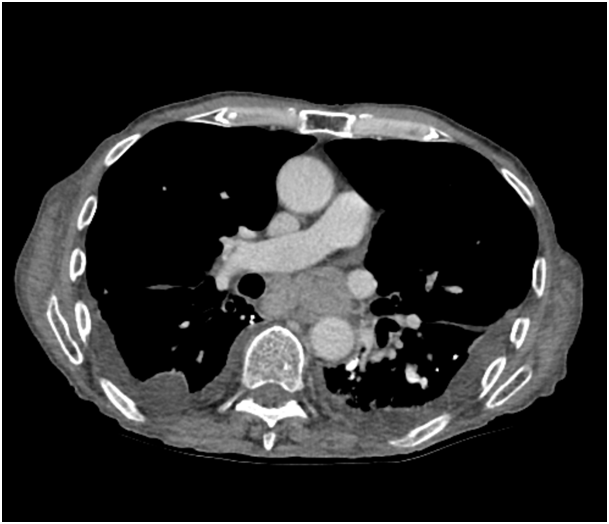

A 77 year old male nursing home resident presented a four week history of dyspnoea, non-productive cough, progressive dysphagia and generalised fatigue. He denied any appetite change or weight loss, fevers or night sweats, chest pain, haemoptysis or wheeze. He was a lifelong non-smoker, exposed to asbestos whilst working in a shoe factory. Clinical examination revealed decreased breath sounds and crackles in the left lower zone, but no peripheral lymphadenopathy or hepatosplenomegaly. Computerised tomography of the chest, abdomen and pelvis was carried out (Figure 1). Bilateral pleural effusions were seen, with left lower lobe consolidation. Meditational and right hilar lymphadenopathy compressing the oesophagus was noted and pleural calcifications suggested previous asbestos exposure.